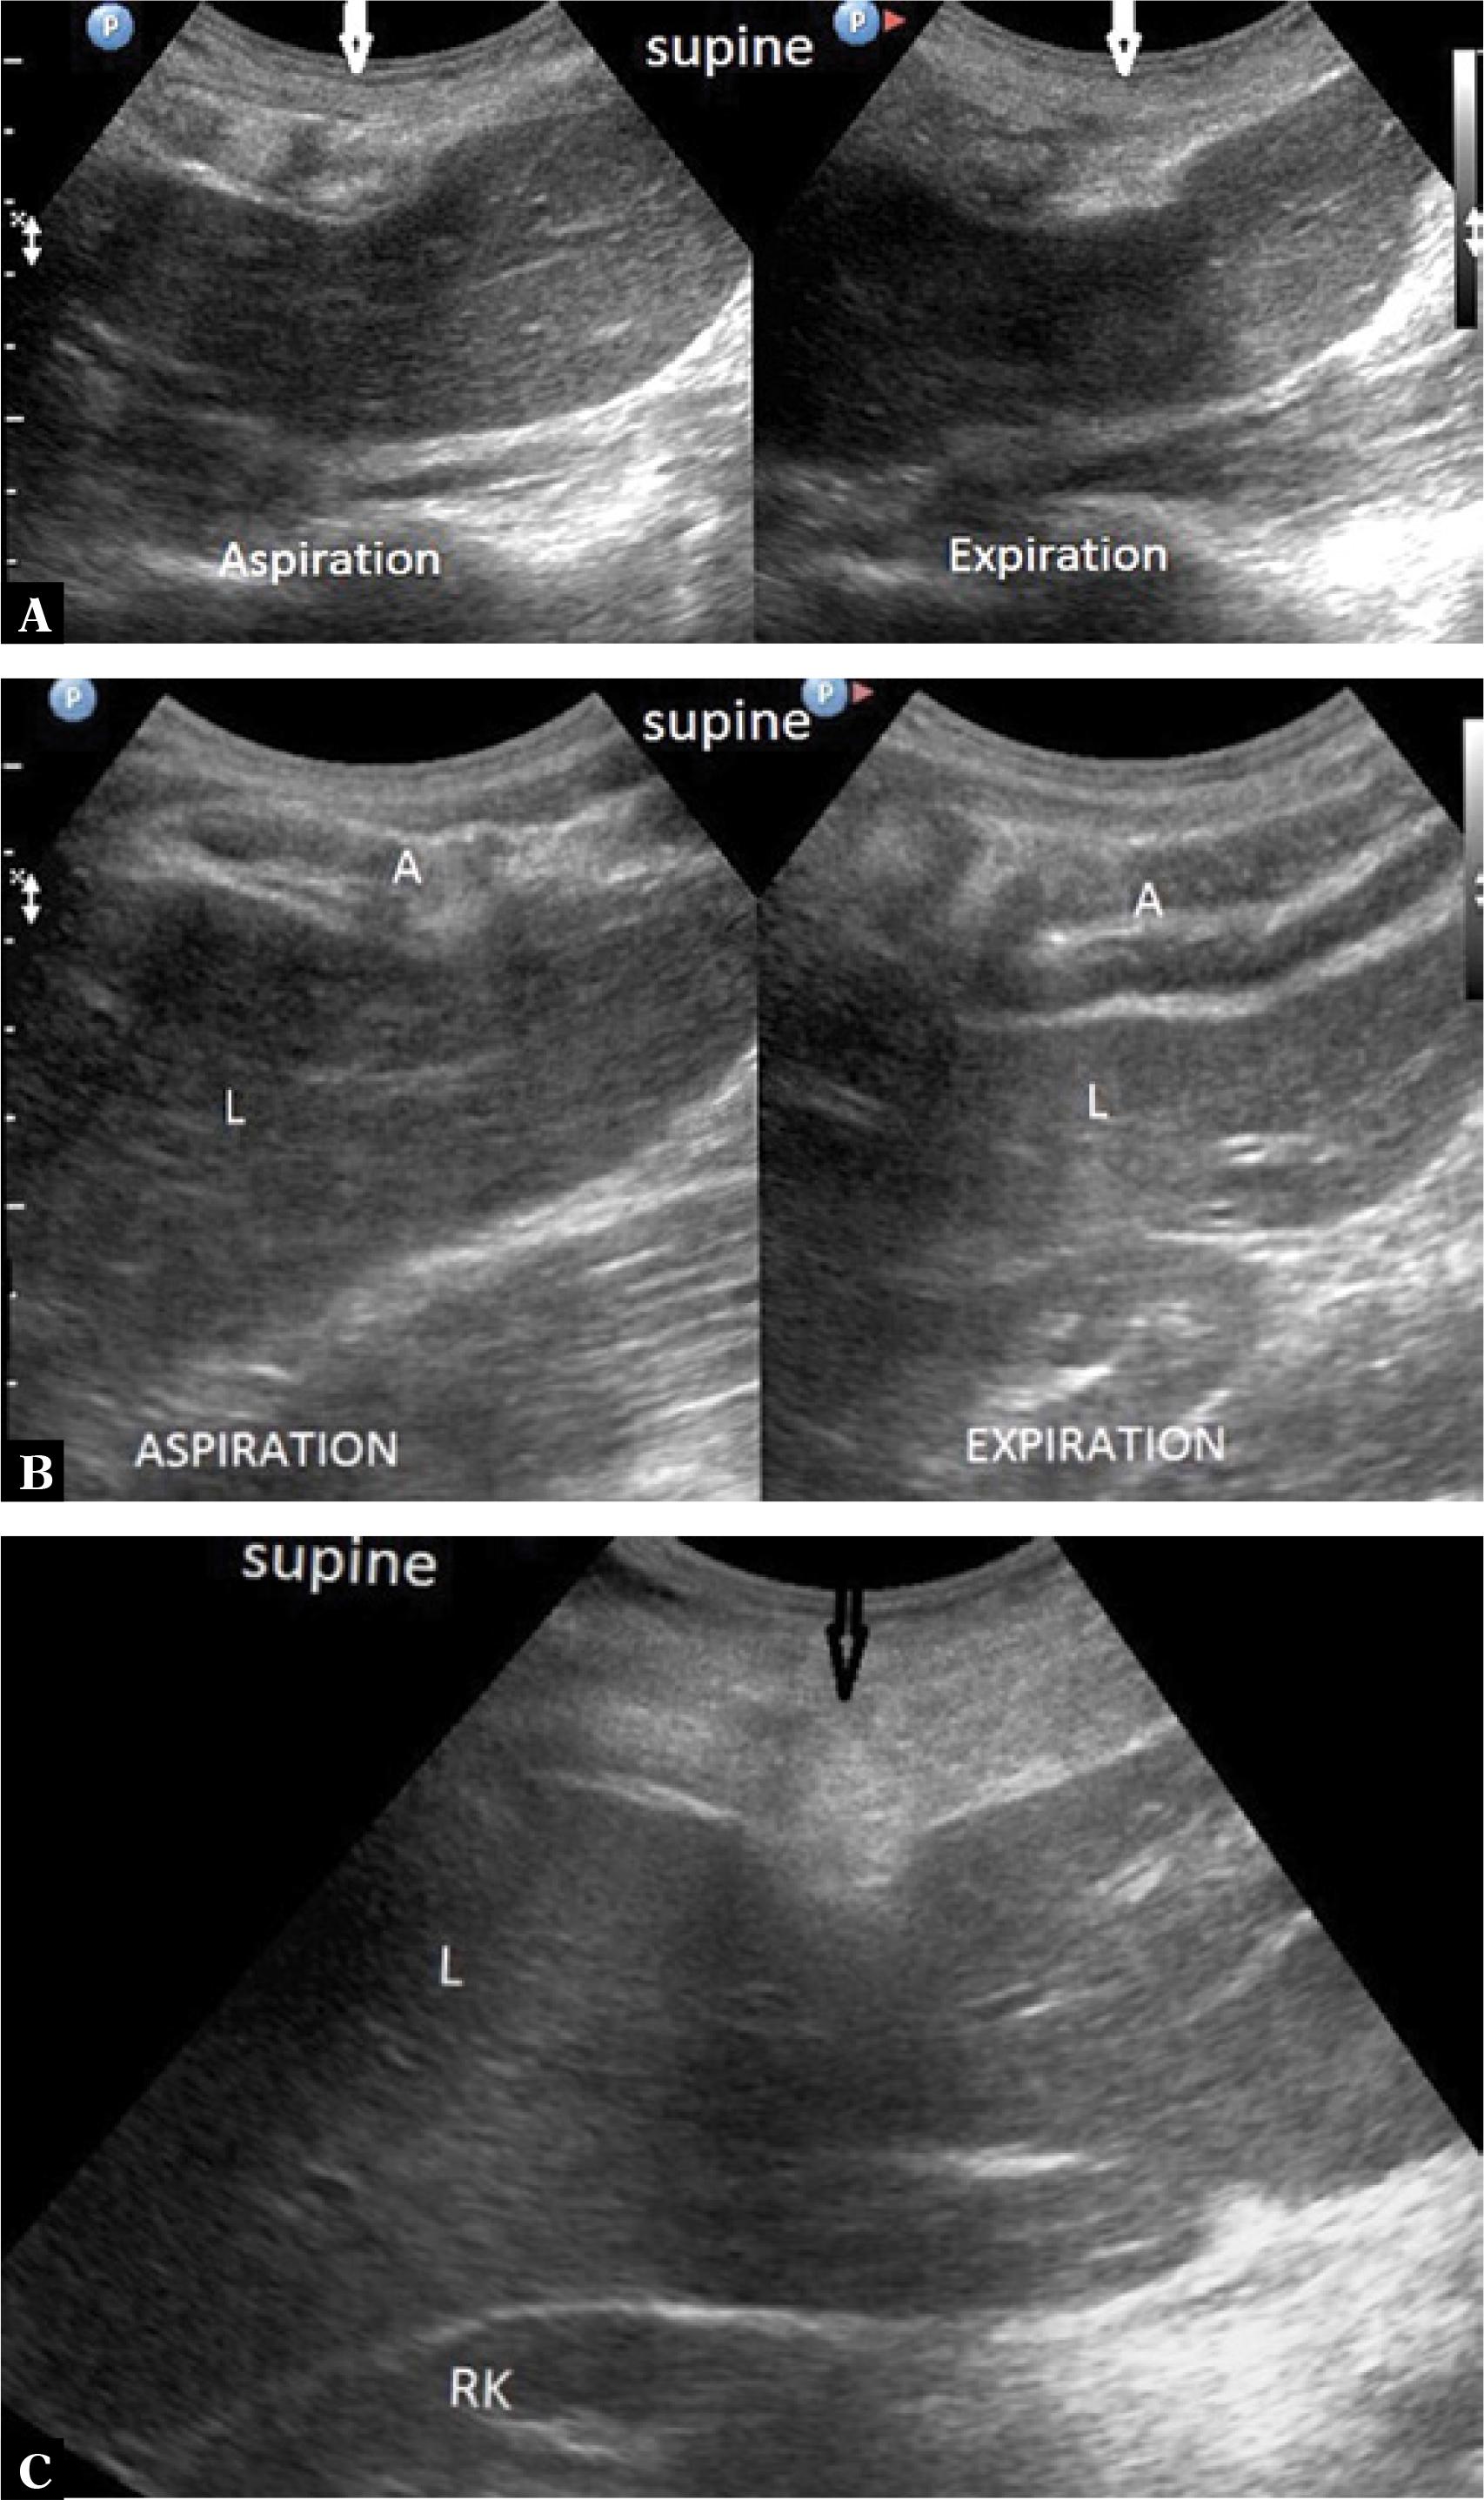

Comparison of the thickness of the musculocartilaginous complex during inhalation, exhalation, supine position, sitting position and forward trunk flexion in 178 patients

| Inhalation | 11–28 mm | 14.5 mm +/− 2.4 | Exhalation | 12–40 mm | 21.5 mm +/− 3.3 |

| Sitting | 11–31 mm | 17.0 mm +/− 2.9 | Flexion | 20–40 mm | 25.4 mm +/− 3.5 |

| Inhalation | 14.5 mm | Exhalation | 21.5 mm |

| Inhalation | 14.5 mm | Sitting | 17.0 mm |

| Inhalation | 14.5 mm | Flexion | 25.4 mm |

| Exhalation | 21.5 mm | Sitting | 17.0 mm |

| Inhalation | 21.5 mm | Flexion | 25.4 mm |

| Sitting | 17.0 mm | Flexion | 25.4 mm |